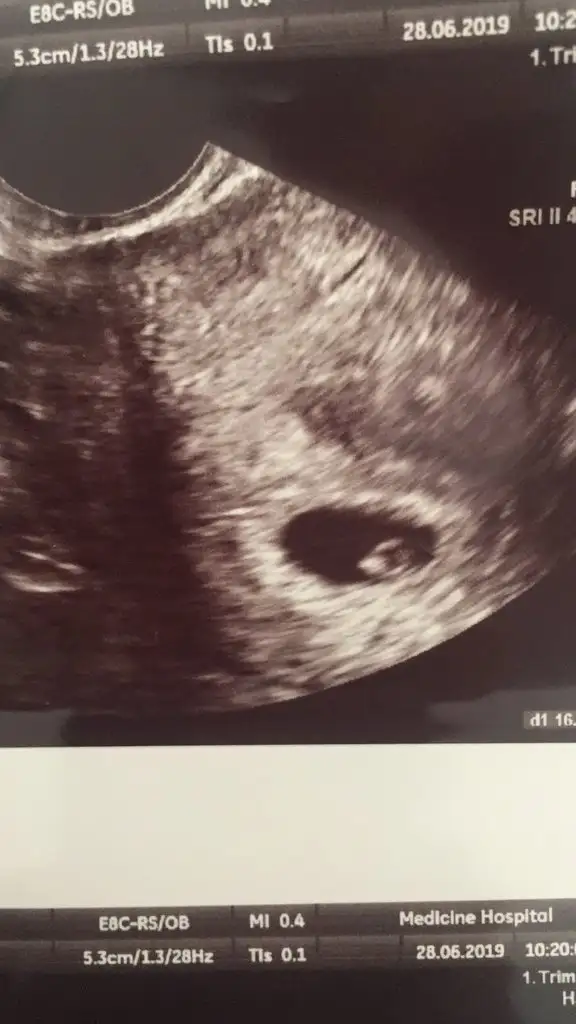

Kizlar banada yorum yaparmisiniz 9 haftalik miniğim karindan ultrason